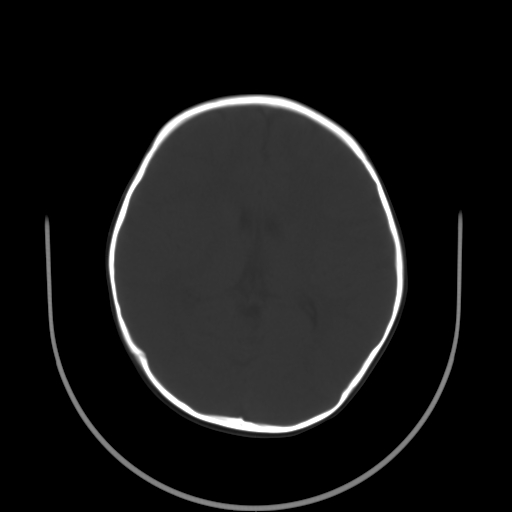

以下是引用深泽交通医院在2009-10-16 8:25:00的发言:[br]右眼环出血伴异物

以下是引用卜一在2009-10-16 15:01:00的发言:[br]右眼球挫裂伤伴异物!

以下是引用拾荒者在2009-10-17 18:38:00的发言:[br]鼻面部皮下积气,右侧睑缘及眼球壁高密度异物影,左侧眼球壁晶状体内侧缘处是圆形低密度影。低密度异物?应提请眼科医生注意。